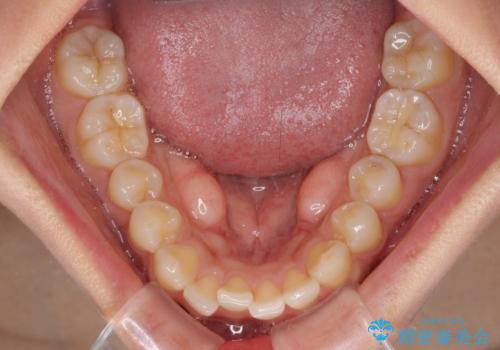

【モニター】歯列が狭くデコボコが気になる 急速拡大装置を用いたインビザライン矯正

- 奥歯の咬み合わせと治療を放置したまま奥歯を気にして来院された患者様です。

上顎骨の幅が下顎骨よりも小さいので、拡大装置により骨幅を広げて上下関係を改善し、その後インビザラインにて歯並びを整えることとしました。

上下の骨幅を改善したことで、スムーズに歯列矯正を行うことができました。

土台のまま放置されていた歯は土台の状態で咬み合っていましたが、急速拡大を行った際に咬み合わせが著しく挙上されたため、その際に土台を大きくすることで咬み合う歯との距離を確保しました。